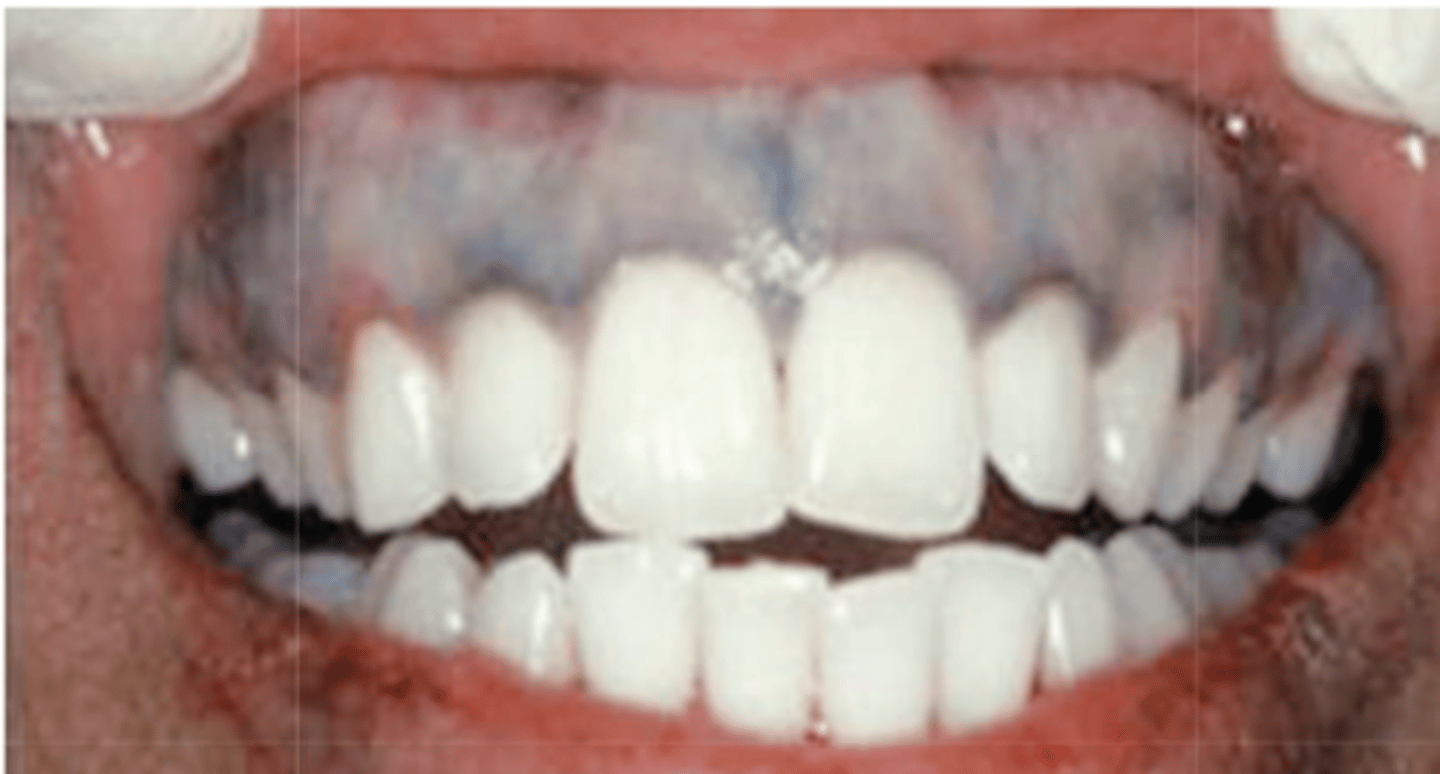

These are clinical features of what pigmented lesion?

- Diffuse, painless, symmetric bluish-gray macule

- Melanonychia and skin lesions

medication-induced pigmentation

What type of pigmented lesion?

medication-induced pigmentation (typically palatal mucosa)